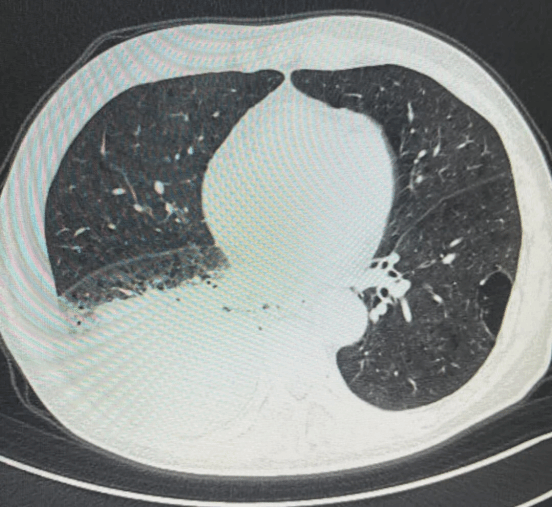

• 精准定位:

依托医学影像设备,实时可视化引导穿刺针精准抵达病灶,避开血管、神经等重要结构。

• 更大组织块:

利用冷冻探针将病变组织“冷冻”取出,相比传统活检获取的组织量更大、结构更完整,为病理分析提供更丰富的样本。